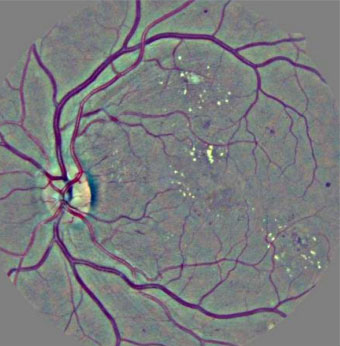

Fond d’œil et détection des lésions liées à la rétinopathie diabétique par l'algorithme de Ophtai, Instant automatic diagnosis of diabetic retinopathy, G Quellec, M Lamard et al. (2019) ©DR

Ces dernières décennies, l’imagerie en ophtalmologie a connu une véritable révolution avec le développement de nouvelles techniques de pointe, l’amélioration de la résolution d’image et l’arrivée de l’intelligence artificielle. L’intelligence artificielle est aujourd’hui de plus en plus utilisée pour aider au diagnostic et transforme la pratique des ophtalmologistes, surtout dans un contexte de difficultés d’accès aux soins. Grâce au deep learning (apprentissage profond), qui donne aux machines la capacité d’apprendre à partir d’une grande quantité de données, l’intelligence artificielle peut interpréter des clichés rétiniens avec une précision parfois supérieure à celle de l’œil humain. Elle est par exemple capable de repérer des vaisseaux sanguins anormaux dans les stades très précoces de la rétinopathie diabétique. De fait, le premier système d’intelligence artificielle à avoir été autorisé par la FDA (Food and Drug Administration) aux Etats-Unis (en 2018), pour une application en santé, est IDx-DR, un outil de dépistage automatisé de la rétinopathie diabétique. Le système permet de dépister les rétines atteintes, de les classer par ordre de sévérité et propose un délai de rendez-vous avec l'ophtalmologiste. En France, l’entreprise Evolucare, en collaboration avec l’AP-HP, l’Inserm et d’autres partenaires, a développé le système d’intelligence artificielle OphtAI. En quelques secondes, OphtAI est capable de détecter par l’analyse de photographies de rétines les signes précoces de la rétinopathie diabétique, ainsi que le risque de glaucome ou de DMLA (sensibilité jusqu’à 99 %). Le système a été entraîné à partir de plus de 760 000 images du réseau de télémédecine Ophdiat de l’AP-HP, qui regroupe une trentaine de centres de dépistage de la rétinopathie diabétique en France (3). Toutefois, OphtAI constitue une aide au diagnostic qui ne peut être utilisé que par un ophtalmologiste, précisent ses concepteurs. Il s’agit du premier logiciel ayant obtenu un marquage CE dans ce domaine en France.

En plus d'être capable de dépister une maladie, l'intelligence artificielle permet également de prédire l’évolution d’une pathologie. En 2021, des chercheurs chinois ont développé un système d’apprentissage profond nommé DeepDR (Deep-learning Diabetic Retinopathy), qui est capable de détecter les différents stades de la rétinopathie diabétique à partir d'images du fond d'œil. Le modèle, entraîné sur des centaines de milliers d’images, permet de prédire le risque d’aggravation de la rétinopathie diabétique et ainsi d’adapter le suivi patient (4).